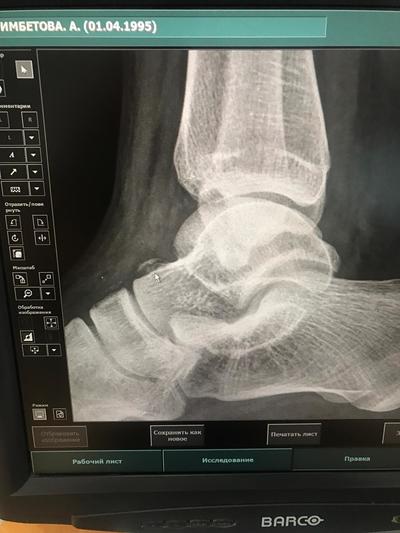

В итоге диагнозом окался - "перелом тарановой кости". Откуда я его узнала? Да потому что мой жених после того как освободился(было бы у него время с утра поехала бы с ним) прихватив друга - травматолога поехали туда же, попросили снимки и поговорили с врачом сами. Если бы не они, возможно я бы не смогла отстоять свое право ходить в гипсе месяц у родителей. Таких случаев было много, такое чувство, если я хожу на прием с родителем(стараюсь сама, но вот такие случаи тоже бывают - до такси сама не допрыгаешь)